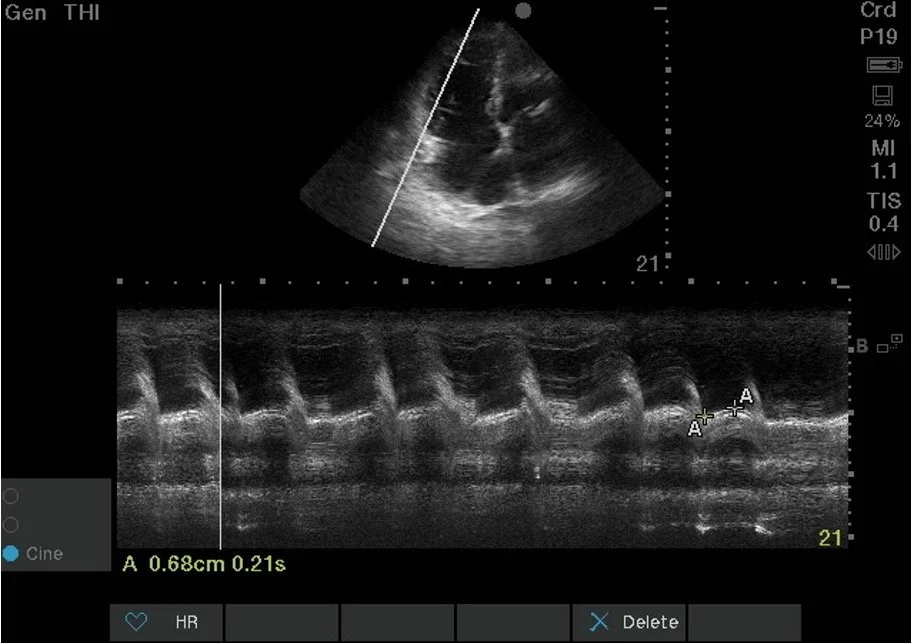

Next, you obtain an apical four chamber view and measure the TAPSE.

Apical Four Chamber